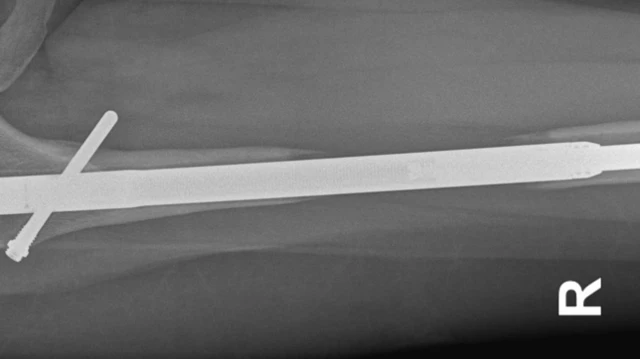

या थोडा त्रास होतो, कारण प्रक्रियेत पायाच्या हाडाचे दोन भाग करून मधे मेटल रॉड बसवला जातो.

हळूहळू त्या हाडांच्या मधे बसवलेल्या मेटल रॉडची लांबी वाढवली जाते, जेणेकरून रुग्णाची लांबी वाढेल.

इलेनची भीती खरी ठरली, दुसऱ्या दिवशी स्कॅन केलं असता त्यांच्या डाव्या पायात लागलेला एक नेल हाडाला छेदून आरपार गेला होता. फेमर (पायाच्या वरच्या भागाचे हाड) तोडून बाहेर आले होते. फेमर शरीरातील सर्वात मजबूत हाड असतं.

सहा आठवड्यांनंतर त्यांचे पाय स्कॅन केले गेले आणि त्यामध्ये उजव्या पायाच्या हाडांची वाढ थांबल्याचं दिसून आलं. या पायात, फेमरचे दोन तुकडे रॉडच्या मदतीने जोडले होते.

इलेन म्हणतात की, "डॉ. गुईशेट यांनी मला सांगितलं की ते पायातील खिळा काढत असताना तो तुटला. त्यांच्याकडे आणखीन एका रुग्णाचा स्क्रू होता. तो स्क्रू ते इलेन यांच्या पायात लावणार होते. पण त्यासाठी होणार खर्च आधीपेक्षा जास्त होता."